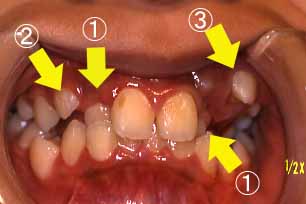

(2)反対咬合,低位咬合

正面

@上の左右の2番目の歯が反対咬合

(中に入っている)

A右上の犬歯(3番目の歯)が

頬より出てきました。

B左上4番目の歯が頬より出て

きました。

(455日目)